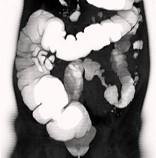

问题 女,56岁,腹胀、腹痛、左下腹包块三月余,无肛门排气,影像检查如图,最可能的诊断是()

选项 A.乙状结肠Crohn病 B.乙状结肠结核 C.乙状结肠腺癌 D.乙状结肠淋巴瘤 E.乙状结肠息肉

答案 C